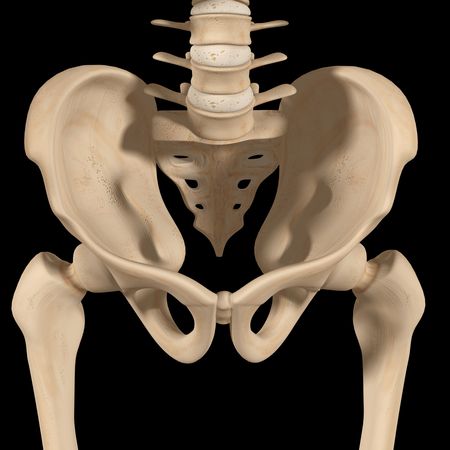

Miednica - jest strukturą pośredniczącą pomiędzy kręgosłupem a kończynami dolnymi. Można ją uznać za jeden z większych tworów kostnych w organizmie. Jej masywna budowa wzięła się z tego, iż odpowiada ona za dźwiganie całego ciężaru górnej części ludzkiego ciała i przenoszenie wywieranego przez nią nacisku na kończyny dolne.

Miednicę tworzą: dwie kości miedniczne, które powstają z połączenia kości łonowej, kulszowej i biodrowej), kość krzyżowa i guziczna.